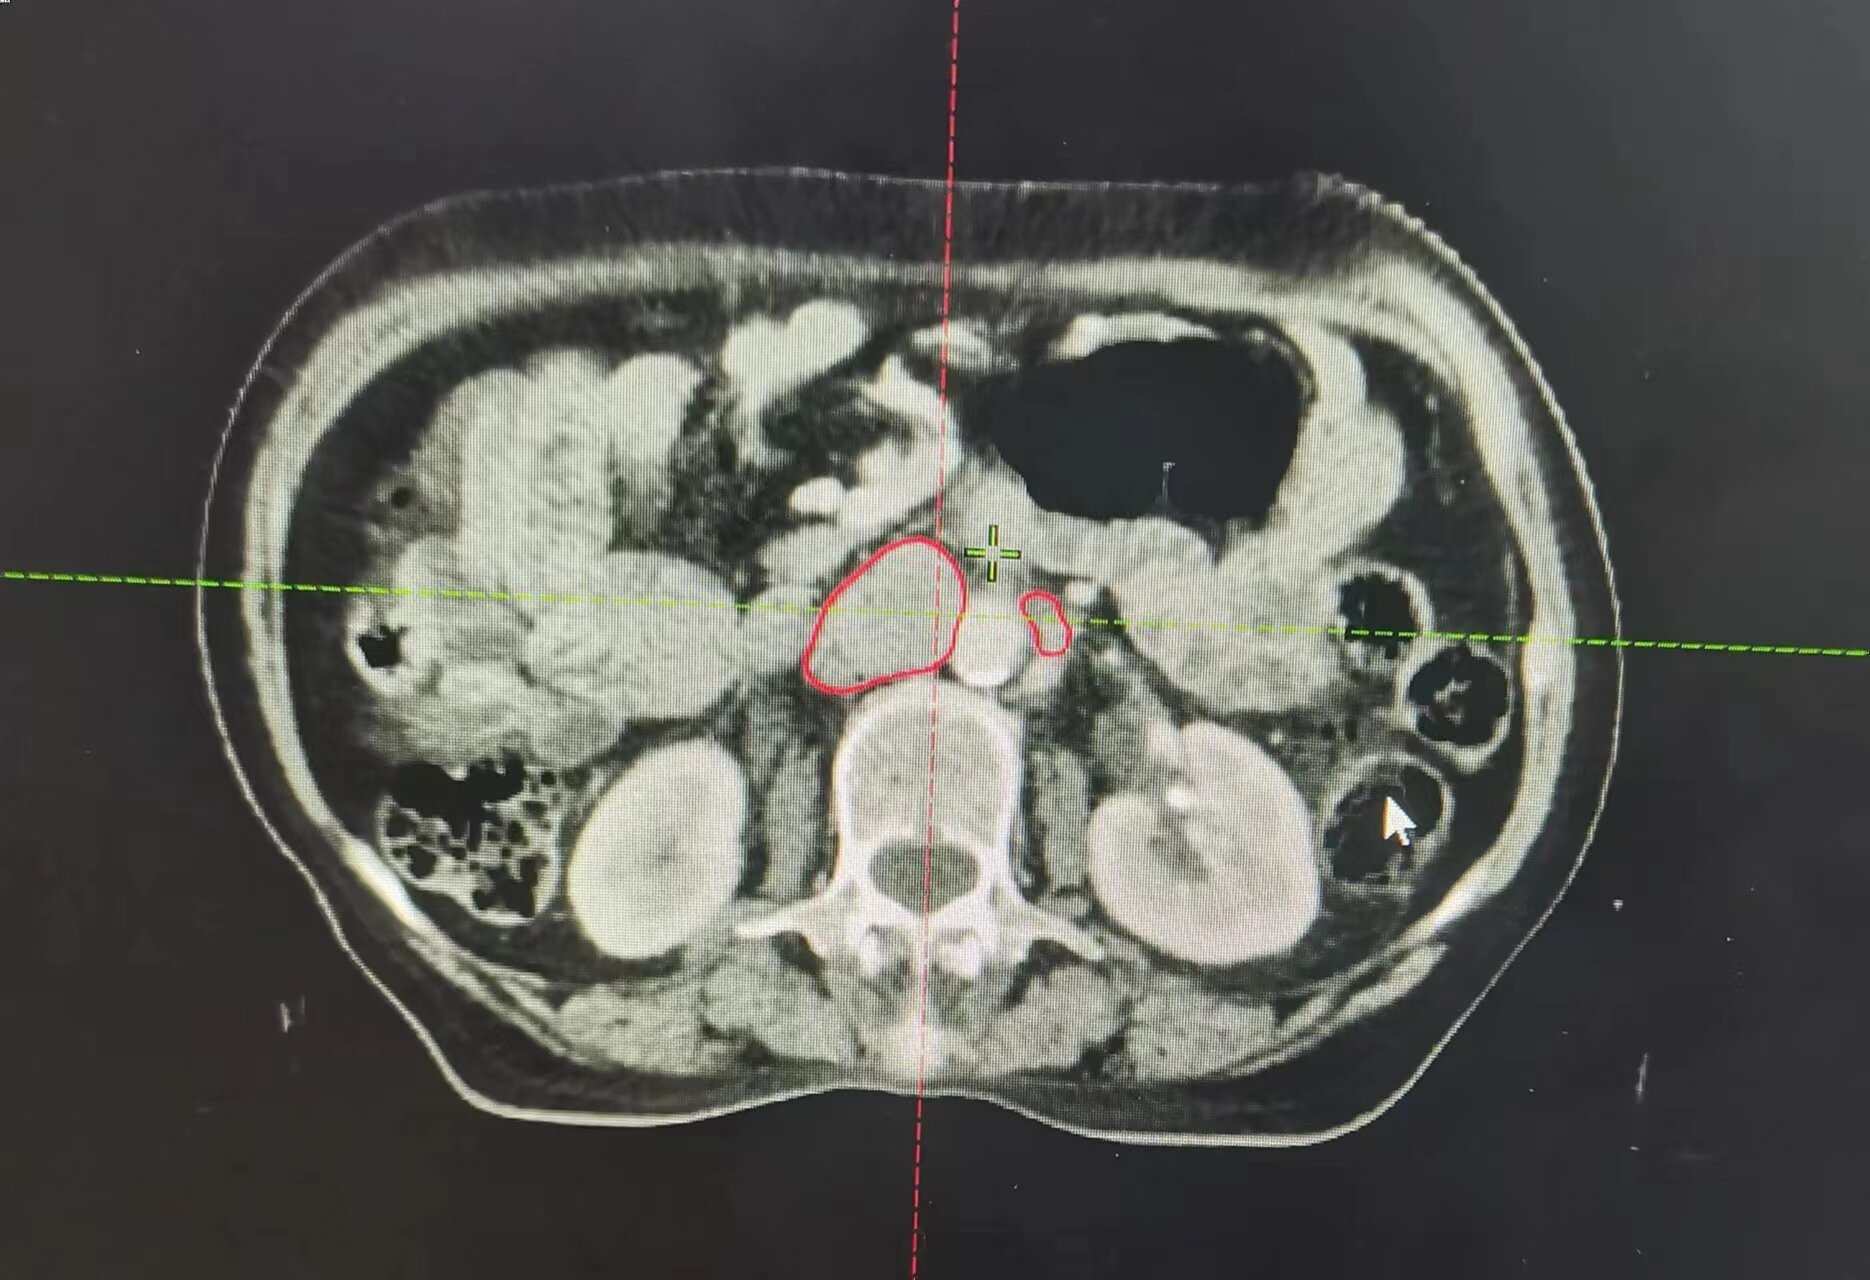

近日,75歲的宮頸癌晚期患者朱阿姨,接受市二院放療科的16次精準(zhǔn)放療后,復(fù)查CT顯示:腹膜后及盆腔轉(zhuǎn)移淋巴結(jié)消失,宮頸腫瘤較前明顯縮小。

朱阿姨被確診宮頸癌后,每天嚴(yán)重的陰道出血及腹部疼痛,使她受盡癌痛的折磨并且心情極度抑郁。3月中旬老人突然腹痛伴陰道大出血,家屬急忙帶朱阿姨來到市二放療科找到趙亮主任,入院后明確診斷為宮頸癌腹膜后及盆腔部位淋巴結(jié)轉(zhuǎn)移。

因老人出血量較大,趙亮接診后立即給予止血治療,出血暫時控制住了,但是腫瘤消不掉,出血現(xiàn)象還是會反復(fù),甚至可能出現(xiàn)危及生命的大出血。考慮到患者病期晚、年齡大、合并基礎(chǔ)疾病多,趙亮帶領(lǐng)科室團(tuán)隊經(jīng)過仔細(xì)討論及評估病情后,決定盡快進(jìn)行三維精準(zhǔn)放射治療及同步化療,同時給予止血及對癥支持治療。